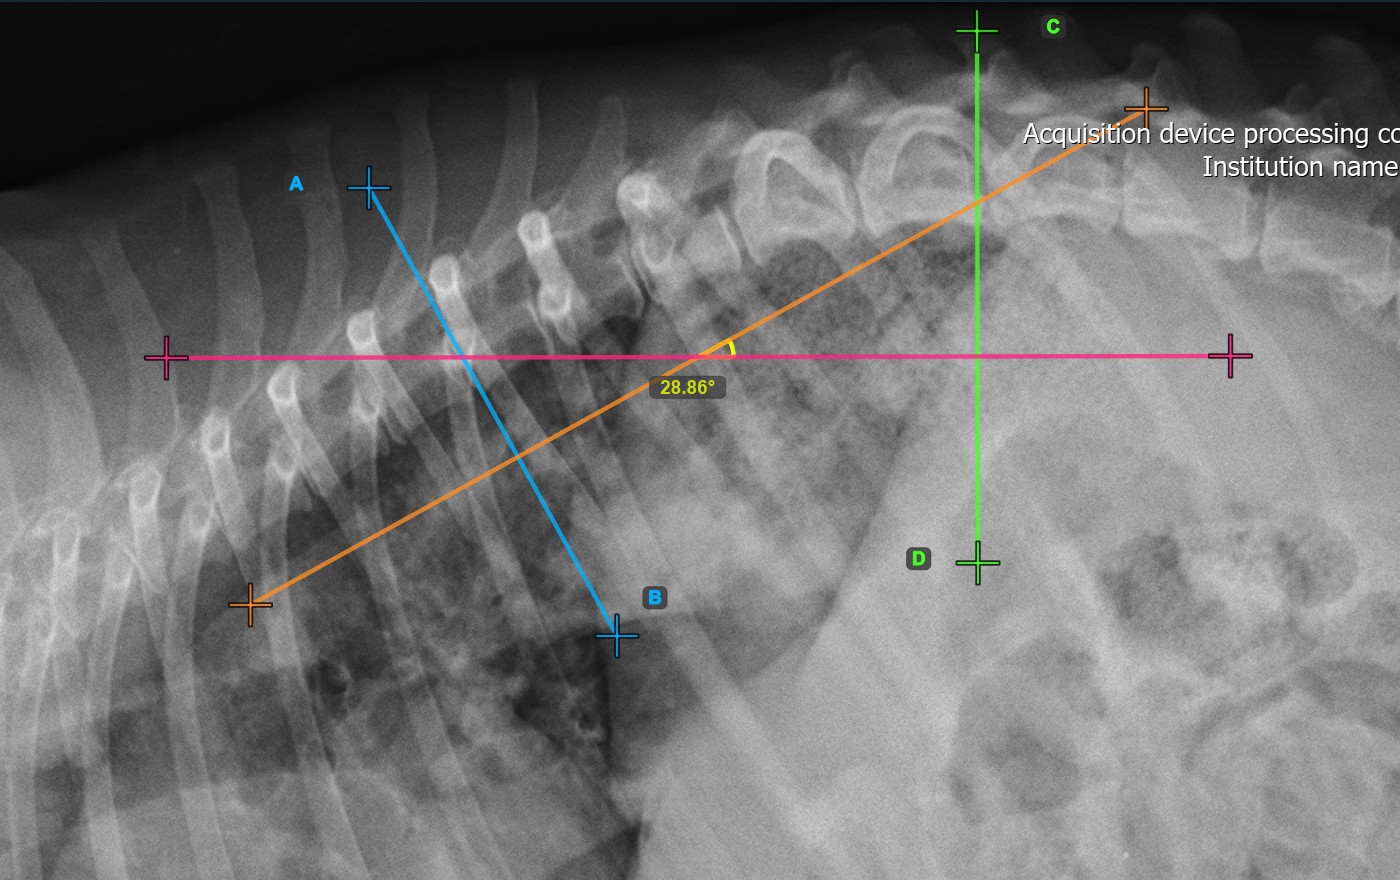

A lenti kép a második csigolya vonal tipikus elhelyezkedését ábrázolja.

../../_images/image374.jpg

Módosítsa a két csigolya vonal helyzetét és irányát a Cobb-szög automatikus újraszámításához.